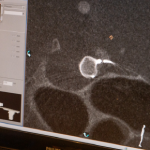

Se trata de artemisse, una diminuta pieza de nitinol (una aleación de níquel y titanio) que se expande como un globo y se ajusta a la forma del aneurisma para reforzar la dilatación anormal de la arteria. El dispositivo rellena el vaso, lo que facilita una trombosis progresiva que terminará por ocluir completamente la vena dañada dejándola sin flujo de sangre. Con esto, los médicos evitan un futuro accidente cerebrovascular hemorrágico, de alta mortalidad.